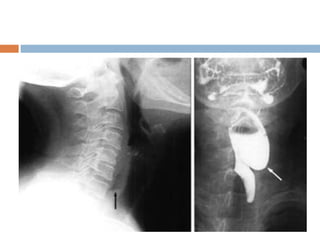

 Plain radiograph of neck

Triangular lucency in the prevertebral tissues with apex at the level of cricoid(due

to air in the upper part of pouch),base has meniscus(due to fluid in the fundus)

Chest x-ray of a 75-year-old patient with a 6-cm Zenker's diverticulum. A,

Before barium swallow. Note the hazy soft tissue mass in the right upper

lung field (arrowheads) representing the Zenker's diverticulum. B, After

barium swallow in the same patient. Air-fluid level can be seen within the

Zenker's diverticulum.